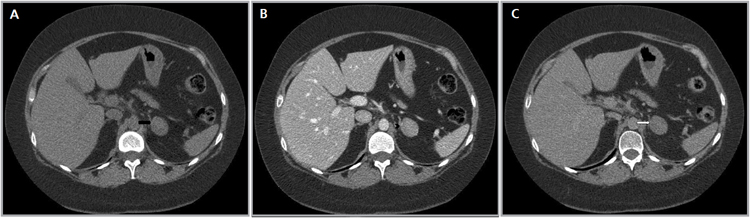

Los valores más utilizados son un 40% de lavado relativo de en fase tardía realizada a los 15 minutos y un lavado absoluto de 60%. De este modo cualquier lesión que muestre un lavado relativo mayor al 40% o absoluto mayor al 60% es consistente con un adenoma, con una sensibilidad y especificidad cercana al 100% (Figura 14 a, b y c). Dado la rapidez con que se obtiene un TAC de abdomen en la actualidad, algunos trabajos han recomendado utilizar cortes tardíos realizados a los 10 minutos, con el fin de optimizar el tiempo de examen, y utilizar un valor relativo de corte más conservador del 50%9.

A

B

C Figura 14. Tomografía computada de un adenoma suprarrenal izquierdo típico. Se ha colocado un circulo que representa la región de interés en la lesión de la glándula suprarrenal izquierda, obteniendo una medición promedio (Avg) expresada en unidades Hounsfield (UH). En fase precontraste (a) su densidad es de 0 UH, (flecha), en fase protovenosa (b) alcanza una densidad de 59 UH (cabeza de flecha), y en fase tardía (c) su lavado es de aproximadamente un 50%, llegando a una densidad de 30 UH.